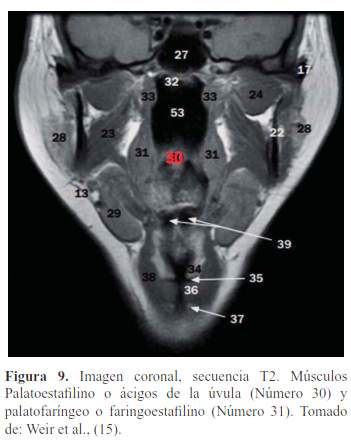

El paladar blando está formado por 5 músculos a cada lado, insertados en el velo, formados de adelante hacia atrás vistas mediante RM (10) (figura 5, figura 6, figura 7, figura 8 y figura 9):

Palatoestafilino o Ácigos de la úvula.

Faringoestafilino o Palatofaríngeo.